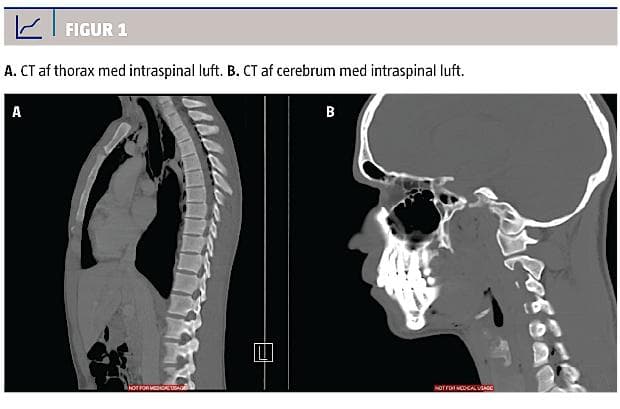

En røntgenoptagelse af thorax viste subkutant emfysem over claviculae og mediastinalt. CT af thorax med intravenøst og peroralt givet kontrast viste subkutant emfysem på collum og i mediastinum samt luft, der strakte sig langs øsofagus dorsalt mod diafragma (Figur 1). Desuden blev der påvist luft intraspinalt og langs enkelte nerverødder på højre side ud til spinalkanalen. Der var ikke mistanke om øsofagusruptur, pneumothorax eller cyster i lungevævet. Ved kontakt til thoraxkirurgisk og neurokirurgisk afdeling blev der anbefalet indlæggelse af patienten til roligt regime og yderligere opfølgning med CT af thorax i det følgende døgn med henblik på observation for progression i luftmængden. En CT-opfølgning dagen efter viste spredning af emfysemet til basis cranii, men ingen luft intrakranialt. Der var på intet tidspunkt neurologiske udfald, og patienten blev udskrevet i klar remission efter tre dages observation.